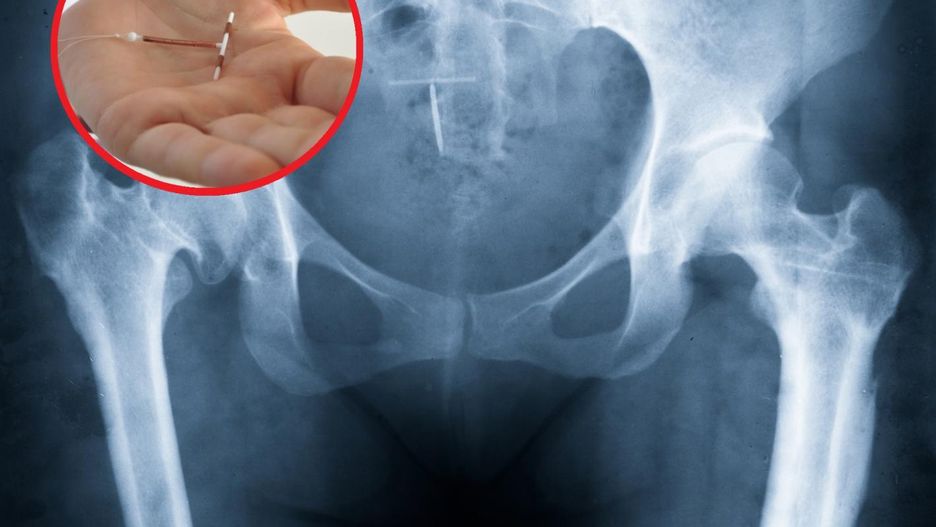

Wkładka domaciczna to popularny środek antykoncepcyjny wśród kobiet. Jej skuteczność według indeksu Pearla (wskaźnika antykoncepcji) wynosi od 0,3 do 2,0. Oznacza to, że ryzyko ciąży jest ograniczone do ponad 98 proc.

Wkładka umieszczana jest w jamie macicy. Może mieć różny kształt i budowę, w zależności od rodzaju. Niegdyś funkcjonowała pod nazwą "spirala" ze względu na swoją początkową formę. Obecnie przypomina raczej nie spiralę, lecz powyginaną literę S albo literę T. Tradycyjna wkładka domaciczna wykonana jest z tworzywa sztucznego, często z dodatkiem miedzi.

Założenie i wyjęcie wkładki może być przeprowadzone tylko przez specjalistów. Samodzielne próby mogą się bowiem zakończyć niepowodzeniem.